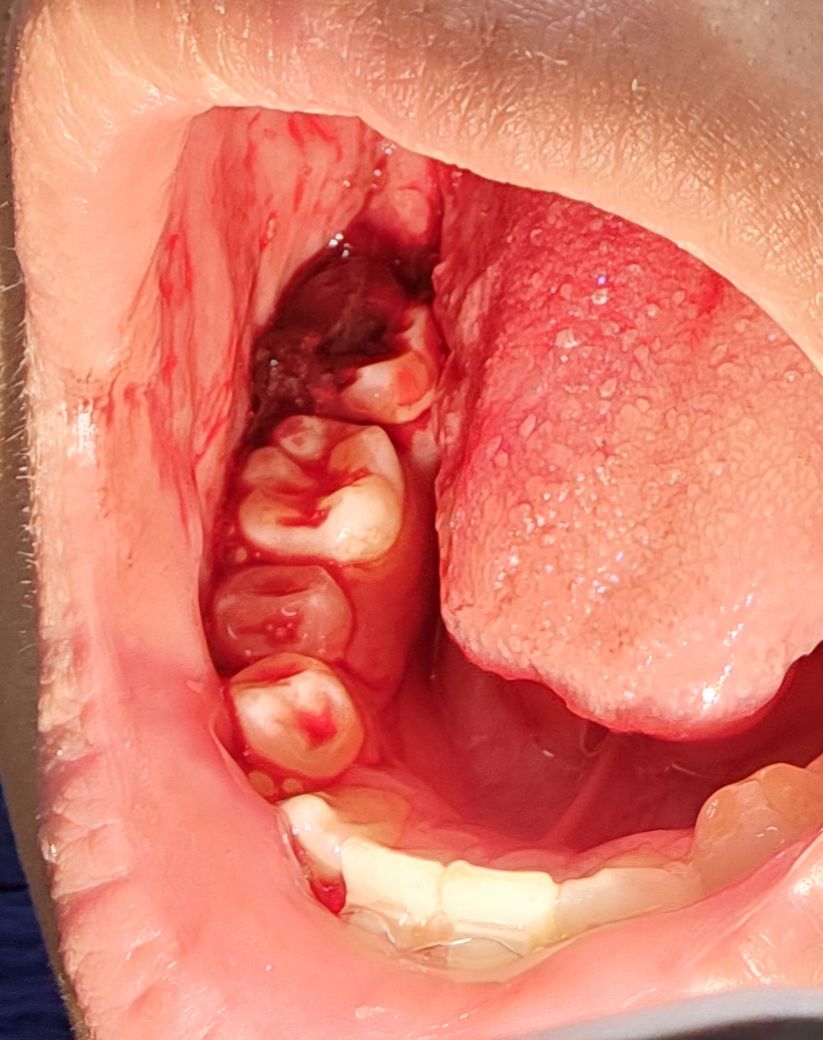

사랑니 발치한지 약 이틀후에 출혈이 생겼는데

23일 화요일에 발치후 24일 수요일에 소독받고 잘 지내다가 25일 새벽에 거울을 봤더니 발치부위, 그 앞 어금니 위에 피가 꽤 많이 묻어있는데 아프거나 하지는 않았고 거즈가 없어서 일단 잠깐 지켜보려고 하니 한 1~2시간 뒤에 발치부위와, 어금니 위에 피들이 굳는거 같아서 새벽이라 일단 잤어요.

현재 일어났을때는 맨 아래 사진과 같은 상황이고 어떻게 해야할지 알려주세요

위가 새벽때 사진, 아래가 아침에 일어났을때 사진입니다